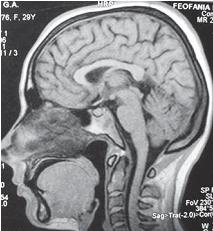

На МРТ № 50 наблюдается гиперлордоз шейного отдела позвоночника с плотным прилеганием спинного мозга к задним отделам спинномозгового канала и выраженными ликвородинамическими нарушениями (что хорошо видно на МРТ головного мозга). В описании снимков я уже неоднократно упоминал характеристики состояния ликворных путей, ликвородинамики. Пожалуй стоит напомнить, что такое ликвор и почему он столь важен для жизнедеятельности организма. Ликвор (лат. liquor — «жидкость») или как его ещё называют цереброспинальная жидкость (лат. cerebrum — «головной мозг»; spinalis — «спинной мозг») — это бесцветная, прозрачная жидкость, заполняющая полости спинного и головного мозга и постоянно циркулирующая в желудочках головного мозга, ликворопроводящих путях, а также субарахноидальном (под паутинной оболочкой) пространстве головного и спинного мозга. В основном ликвор образуется в желудочках головного мозга за счёт секреции сосудистых сплетений, а также в эпендиме (греч. ependyma — «верхний покров»; тонкая оболочка, выстилающая желудочки головного мозга и центральный канал спинного мозга) и мозговой паренхиме. Всего мозговая паренхима с её капиллярным эндотелием создает около 10 % ликвора. В сутки образуется около 500 мл ликвора. Обновляется он в течение этого времени от 3 до 7 раз! Обращаю на это внимание особенно тех людей, которые испытывают психологический страх перед проведением такой лабораторной процедуры, как спинномозговая пункция (пункция субарахноидального пространства спинного мозга, люмбальная пункция, поясничный прокол) с диагностической или лечебной целью. При соблюдении всех предосторожностей эта процедура практически безопасна. Приблизительно через два часа ликвор полностью восстанавливается! Наибольшее количество ликвора находится в системе мозговых желудочков и в поясничном расширении спинномозгового канала. Кстати, ликвор, находящийся в поясничной области субарахноидального пространства спинного мозга, перемещается краниально (вверх) и достигает базальных цистерн в течение одного часа. Линейная скорость циркуляции ликвора довольно мала — всего около 0,3–0,5 см/мин, а объёмная — 0,2–0,7 мл/мин. Ликвор циркулирует в желудочках и над поверхностями головного и спинного мозга. Он связан с кровью непосредственно через гематоэнцефалический барьер (греч. haima — «кровь», enkephalos — «мозг»; физиологический механизм, регулирующий обмен веществ между кровью, ликвором и мозгом), арахноидальную мембрану (arachnoidea — «паутинная оболочка головного или спинного мозга»; греч. arachne — «паук», eidos — «вид, сходство»), ворсинки паутинной оболочки, через сплетения и внеклеточную жидкость мозговой паренхимы (греч. parechyma, от para — «возле», enchyma — «влитое, разлитое»; специфическая ткань какого-либо органа, выполняющая основную функцию этого органа). |